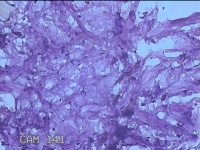

性别

女

年龄

36岁

临床诊断

皮肤良性肿瘤

发现左侧大腿息肉组织2年余,无明显疼痛及不适。

左侧大腿息肉组织

大体所见

灰白粉红色息肉样组织4.3x3.3x0.8cm一块,表面光滑,切开组织呈实性,切面灰白粉红色,质软。

图1